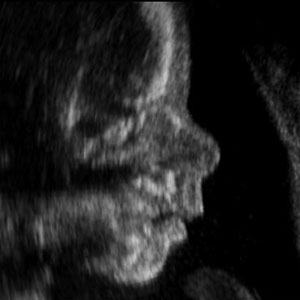

A fetus can sense mom’s psychological state

FetusAs a fetus grows, it’s constantly getting messages from its mother. It’s not just hearing her heartbeat and whatever music she might play to her belly; it also gets chemical signals through the placenta. A new study, which will be published in Psychological Science, a journal of the Association for Psychological Science, finds that this includes signals about the mother’s mental state. If the mother is depressed, that affects how the baby develops after it’s born.